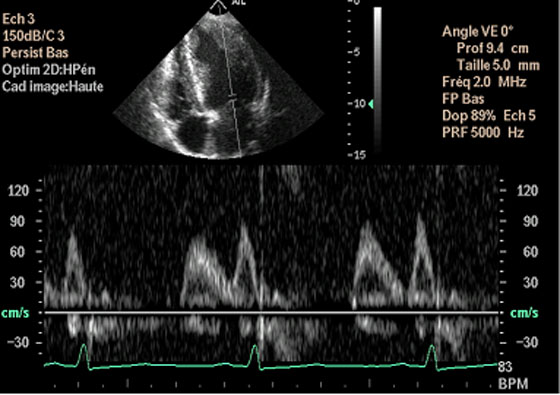

- 7 - Echocardiographie - Doppler